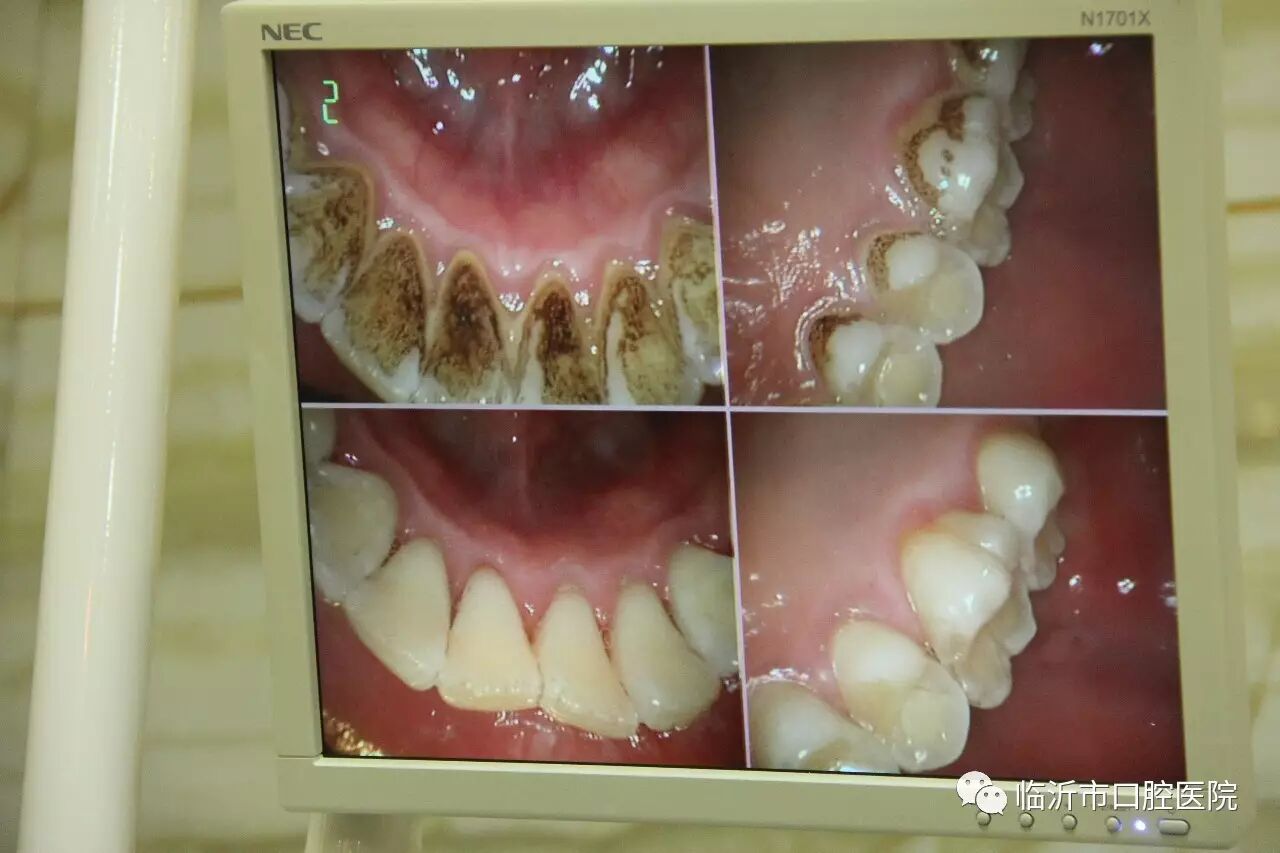

牙结石又称牙石,通常存在于唾液腺开口处的牙齿表面。如下颚前牙的舌侧表面,上颚后牙的颊侧表面和牙齿的颈部,以及口腔黏膜运动不到的牙齿表面等处。牙结石最开始是乳白色的软垢,通过逐渐钙化变硬。它是由75%的磷酸钙,15%~25%的水、有机物、磷酸锰、矿酸钙及微量的钾、钠、铁所构成。牙结石通常呈现出黄色、棕色、或黑色等,有的与自然牙颜色相近,有的则明显可见差异

牙结石一旦钙化,就等同于在口腔中落地生根,建立了生存的基地。但这位大恶魔并不会就此止步,而是继续开枝散叶、呼朋引伴,随着时间的推移越积越多、越级越厚,并逐渐向牙颈部位发展,形成更为隐形也更为可怕的“龈下结石”。

牙结石从牙冠逐渐向下蔓延,牙结石每进步一些,牙槽骨就萎缩一些,久而久之,牙齿就逐渐松动,牙结石便见缝插针,逐渐蔓延到牙根部位。对口腔而言,结石是一种异物,它的存在本身就会不断刺激牙周组织并压迫牙龈,影响口腔局部血液循环,造成牙周组织病菌感染,引起牙龈发炎萎缩,形成牙周袋。当牙周袋形成后,食物残渣、牙菌斑和结石等更易堆积,进一步的破坏更深的牙周膜,如此不断的恶性循环的结果,终至牙周支持组织全部破坏殆尽,牙龈出血、牙周疾病等随之而来。总而言之,如不能及时清除,被牙结石缠上的牙齿最终逃脱不了溃烂脱落的命运。